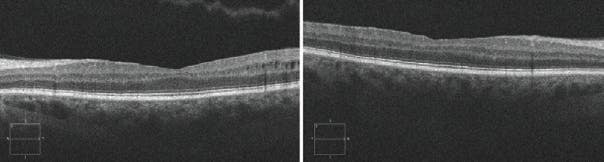

<p>Figure 2. Fluorescein angiography revealed several findings, including delayed arteriovenous filling time, peripheral nonperfusion, neovascularization leakage, and leaking microaneurysms in the macula.</p>

Figure 2. Fluorescein angiography revealed several findings, including delayed arteriovenous filling time, peripheral nonperfusion, neovascularization leakage, and leaking microaneurysms in the macula.

Examination revealed UCVA of 20/25 OD and 20/15 OS, normal IOPs, and well-centered IOLs. Dilated fundus examination revealed asteroid hyalosis in the right eye, clear vitreous in the left eye, and healthy nerves with a cup-to-disc ratio of 0.3 in each eye. Both eyes had prominent arteriovenous nicking changes, diffuse dot-blot hemorrhages in all peripheral quadrants, mild venous engorgement, and neovascularization along the superior and inferior temporal arcades. Rare macular dot-blot hemorrhages were appreciated (Figure 1). Fluorescein angiography revealed delayed arteriovenous filling time, peripheral nonperfusion, several areas of neovascularization leakage, and leaking microaneurysms in the macula (Figure 2). OCT revealed trace macular edema (Figure 3).

Fluorescein angiography in OIS will demonstrate a prolonged arm-to-choroid and arm-to-retina circulation time, with the affected eyes in 60% of patients taking a minute or longer to fill. The most sensitive sign is prolonged retinal arteriovenous time, present in 95% of cases. This, however, is nonspecific. Staining of major retinal vessels and their branches in late phase angiography is seen in 85% of eyes, possibly due to endothelial cell damage secondary to chronic ischemia.1